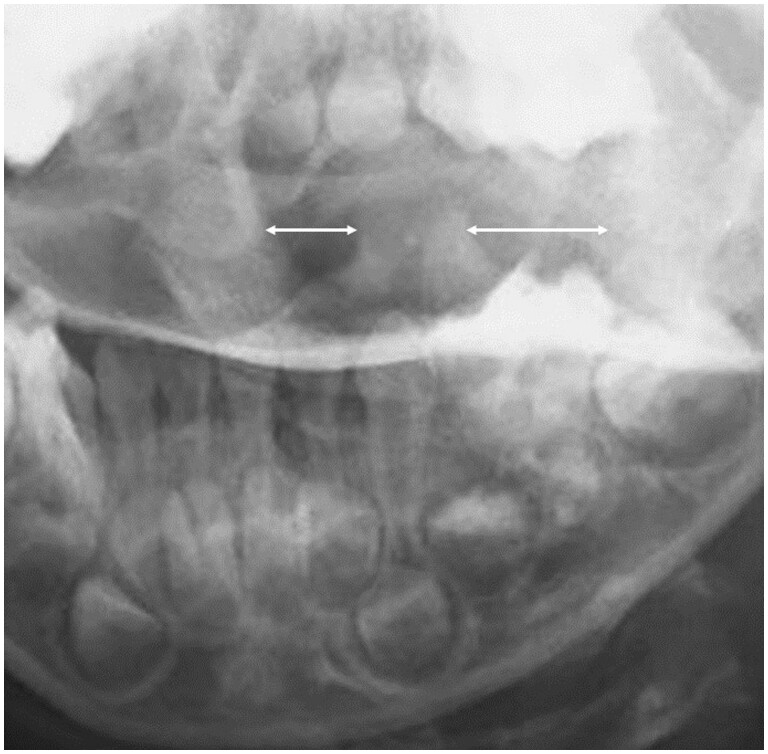

Various respiratory, musculoskeletal, gastrointestinal, neurological, and urinary complications have been reported in Kawasaki disease. Here, we describe a rare case of atlantoaxial rotatory fixation (AARF) associated with incomplete Kawasaki disease. The case is of a healthy 4-year-old Japanese boy who had a high-grade fever, lymphadenopathy, and torticollis diagnosed with incomplete Kawasaki disease. Intravenous high-dose immunoglobulin and oral aspirin quickly resolved his fever and improved his lymphadenopathy, but torticollis remained. On orthopaedic examination, torticollis was observed with a marked restriction of rotation, and an open-mouth anteroposterior cervical radiograph and a CT scan confirmed rotational dislocation at the dens axis (AARF). Cervical collar fixation was immediately started, and the torticollis gradually normalized within a week. AARF is defined as torticollis due to dislocation or subluxation of the atlantoaxial joint. The diagnosis of AARF is difficult with routine plain cervical radiographs in 2 directions alone, and an additional cervical open-mouth anteroposterior radiograph and a CT scan aid the diagnosis. AARF associated with Kawasaki disease is uncommon, and only 24 cases have been reported in the literature. AARF may occur in Kawasaki disease patients with cervical lymphadenopathy. Still, torticollis is often transient and may not be recognized or ignored by family doctors and paediatricians. Reduction of the atlantoaxial joint can often be achieved spontaneously or with conservative treatment such as a collar or neck traction, but treatment is difficult if the diagnosis is delayed. Therefore, family doctors and paediatricians need to suspect the onset of AARF if torticollis is observed during treatment for Kawasaki disease, perform plain cervical radiographs including open-mouth anteroposterior view and a CT scan of the cervical spine, and have orthopaedists immediately intervene to avoid invasive surgery.